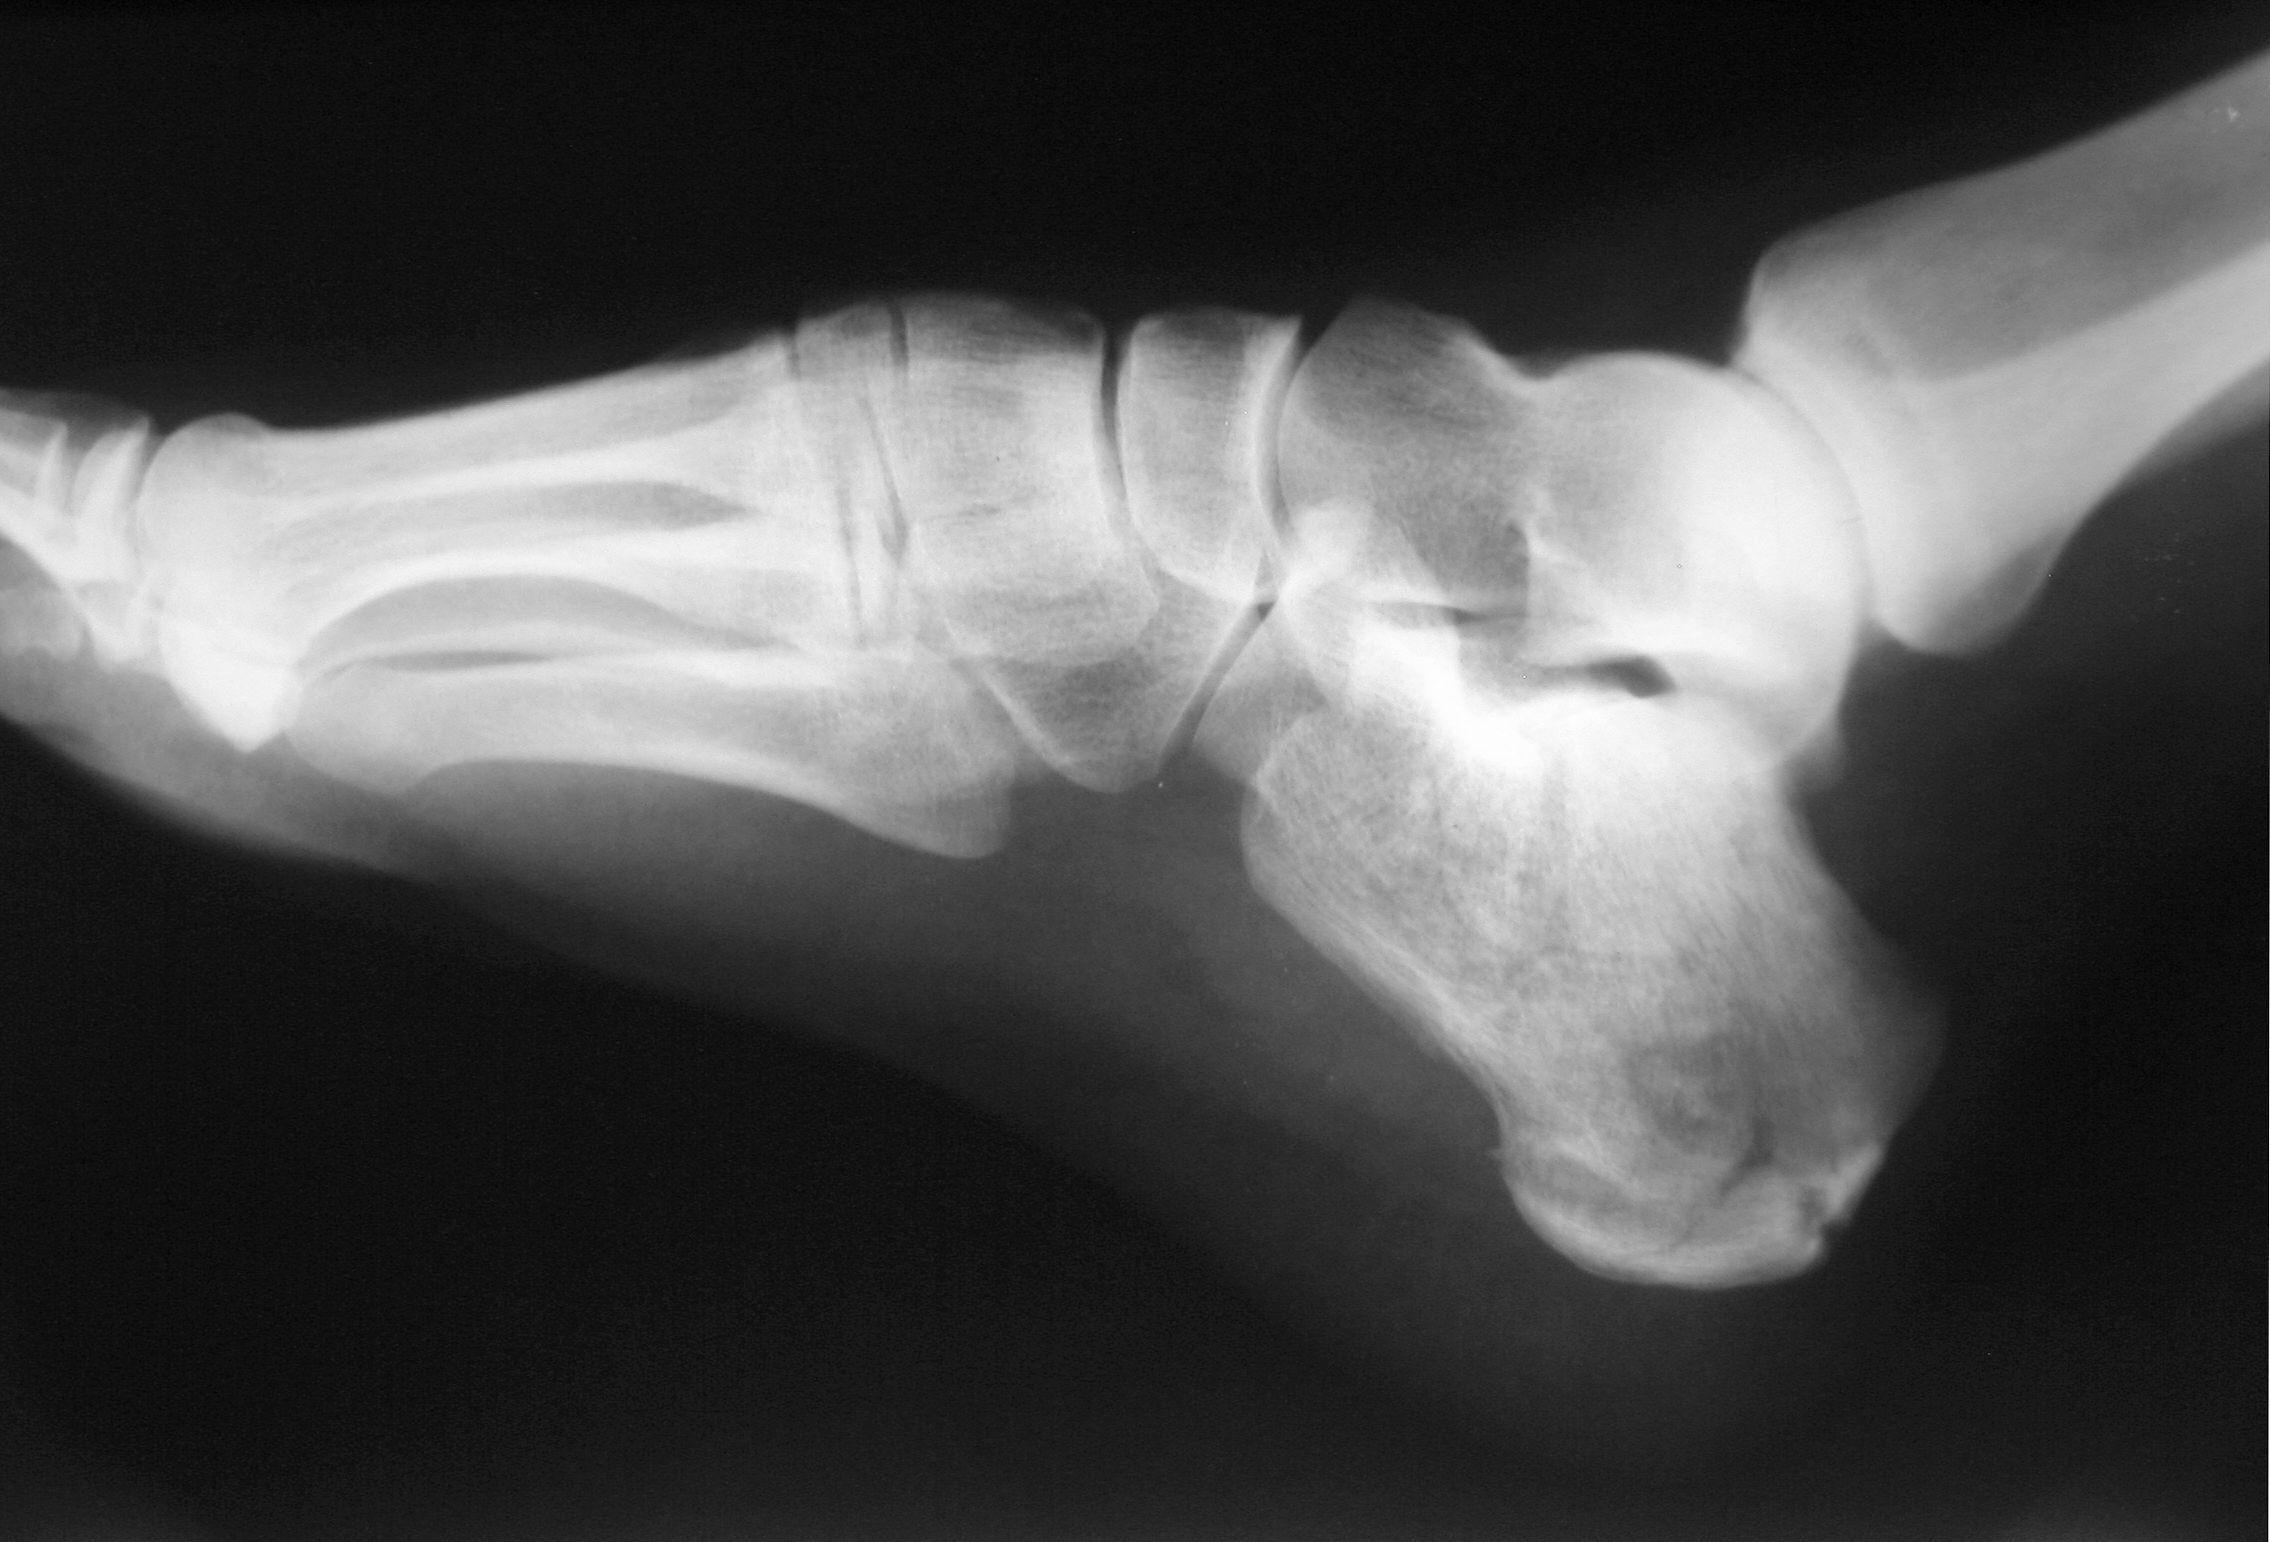

Fracture calcaneus, talus, autres os du tarse

Avis chirurgical.

Complément d’imagerie par

TDM du pied

.